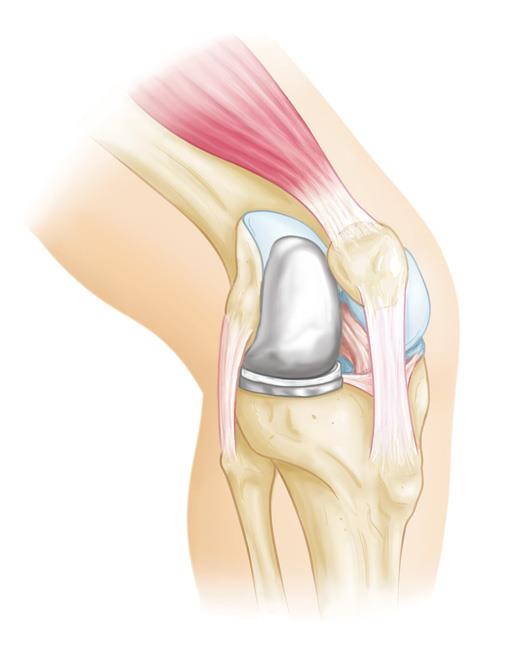

Knee Replacement Surgery

This is a procedure that involves removing diseased or damaged bone along with cartilage of a knee joint and further replacing them with an artificial joint that is made of metal, polymers, or high-grade plastic parts.

Partial Knee Replacement

Your doctor might advise a partial knee replacement, also referred to as a unicompartmental knee replacement, if you are suffering from severe knee discomfort that prevents you from performing your daily activities.

Robotic Knee Replacement Surgery

A robotic knee replacement surgery is similar to a traditional knee replacement. In this surgery, the surgeon will remove the damaged tissue in the knee and replace it with an artificial joint. Here in this surgery is usually performed with assistance from a robotic arm or handheld robotic device (depending on the robotic system used for the surgery).